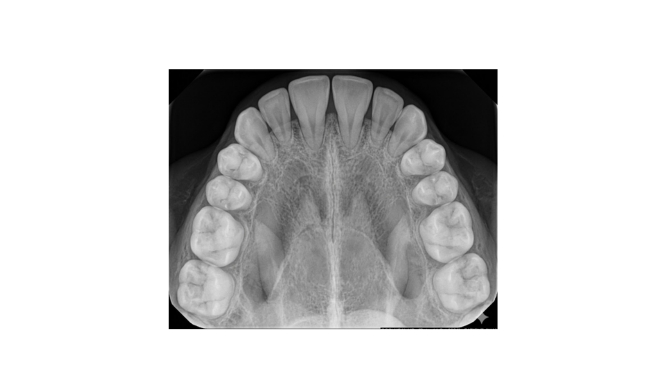

🦷 ¿Qué es una radiografía oclusal?

La radiografía oclusal captura una imagen más amplia del maxilar o la mandíbula, enfocándose en la superficie de mordida.

👉 Es ideal para observar zonas completas de la boca, no solo un diente.

📌 ¿Cuándo se utiliza?

Este estudio se recomienda en situaciones donde se necesita una visión más global:

✔️ Evaluar dientes retenidos (que no han salido)

✔️ Detectar quistes o tumores

✔️ Analizar fracturas en el hueso

✔️ Revisar el desarrollo dental en niños

✔️ Localizar objetos extraños

✔️ Estudiar anomalías estructurales